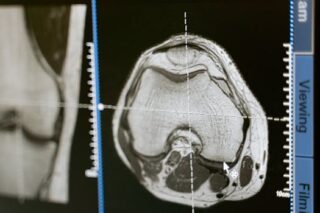

Kidney cysts are typically discovered inadvertently during imaging tests conducted for other health reasons. These include ultrasounds, CT scans, or MRIs. Patients usually have these tests due to abdominal pain, hematuria, or other unrelated health concerns. If your healthcare provider discovers a cyst, they will assess the cyst’s characteristics, including size, shape, and composition, to determine the next steps.